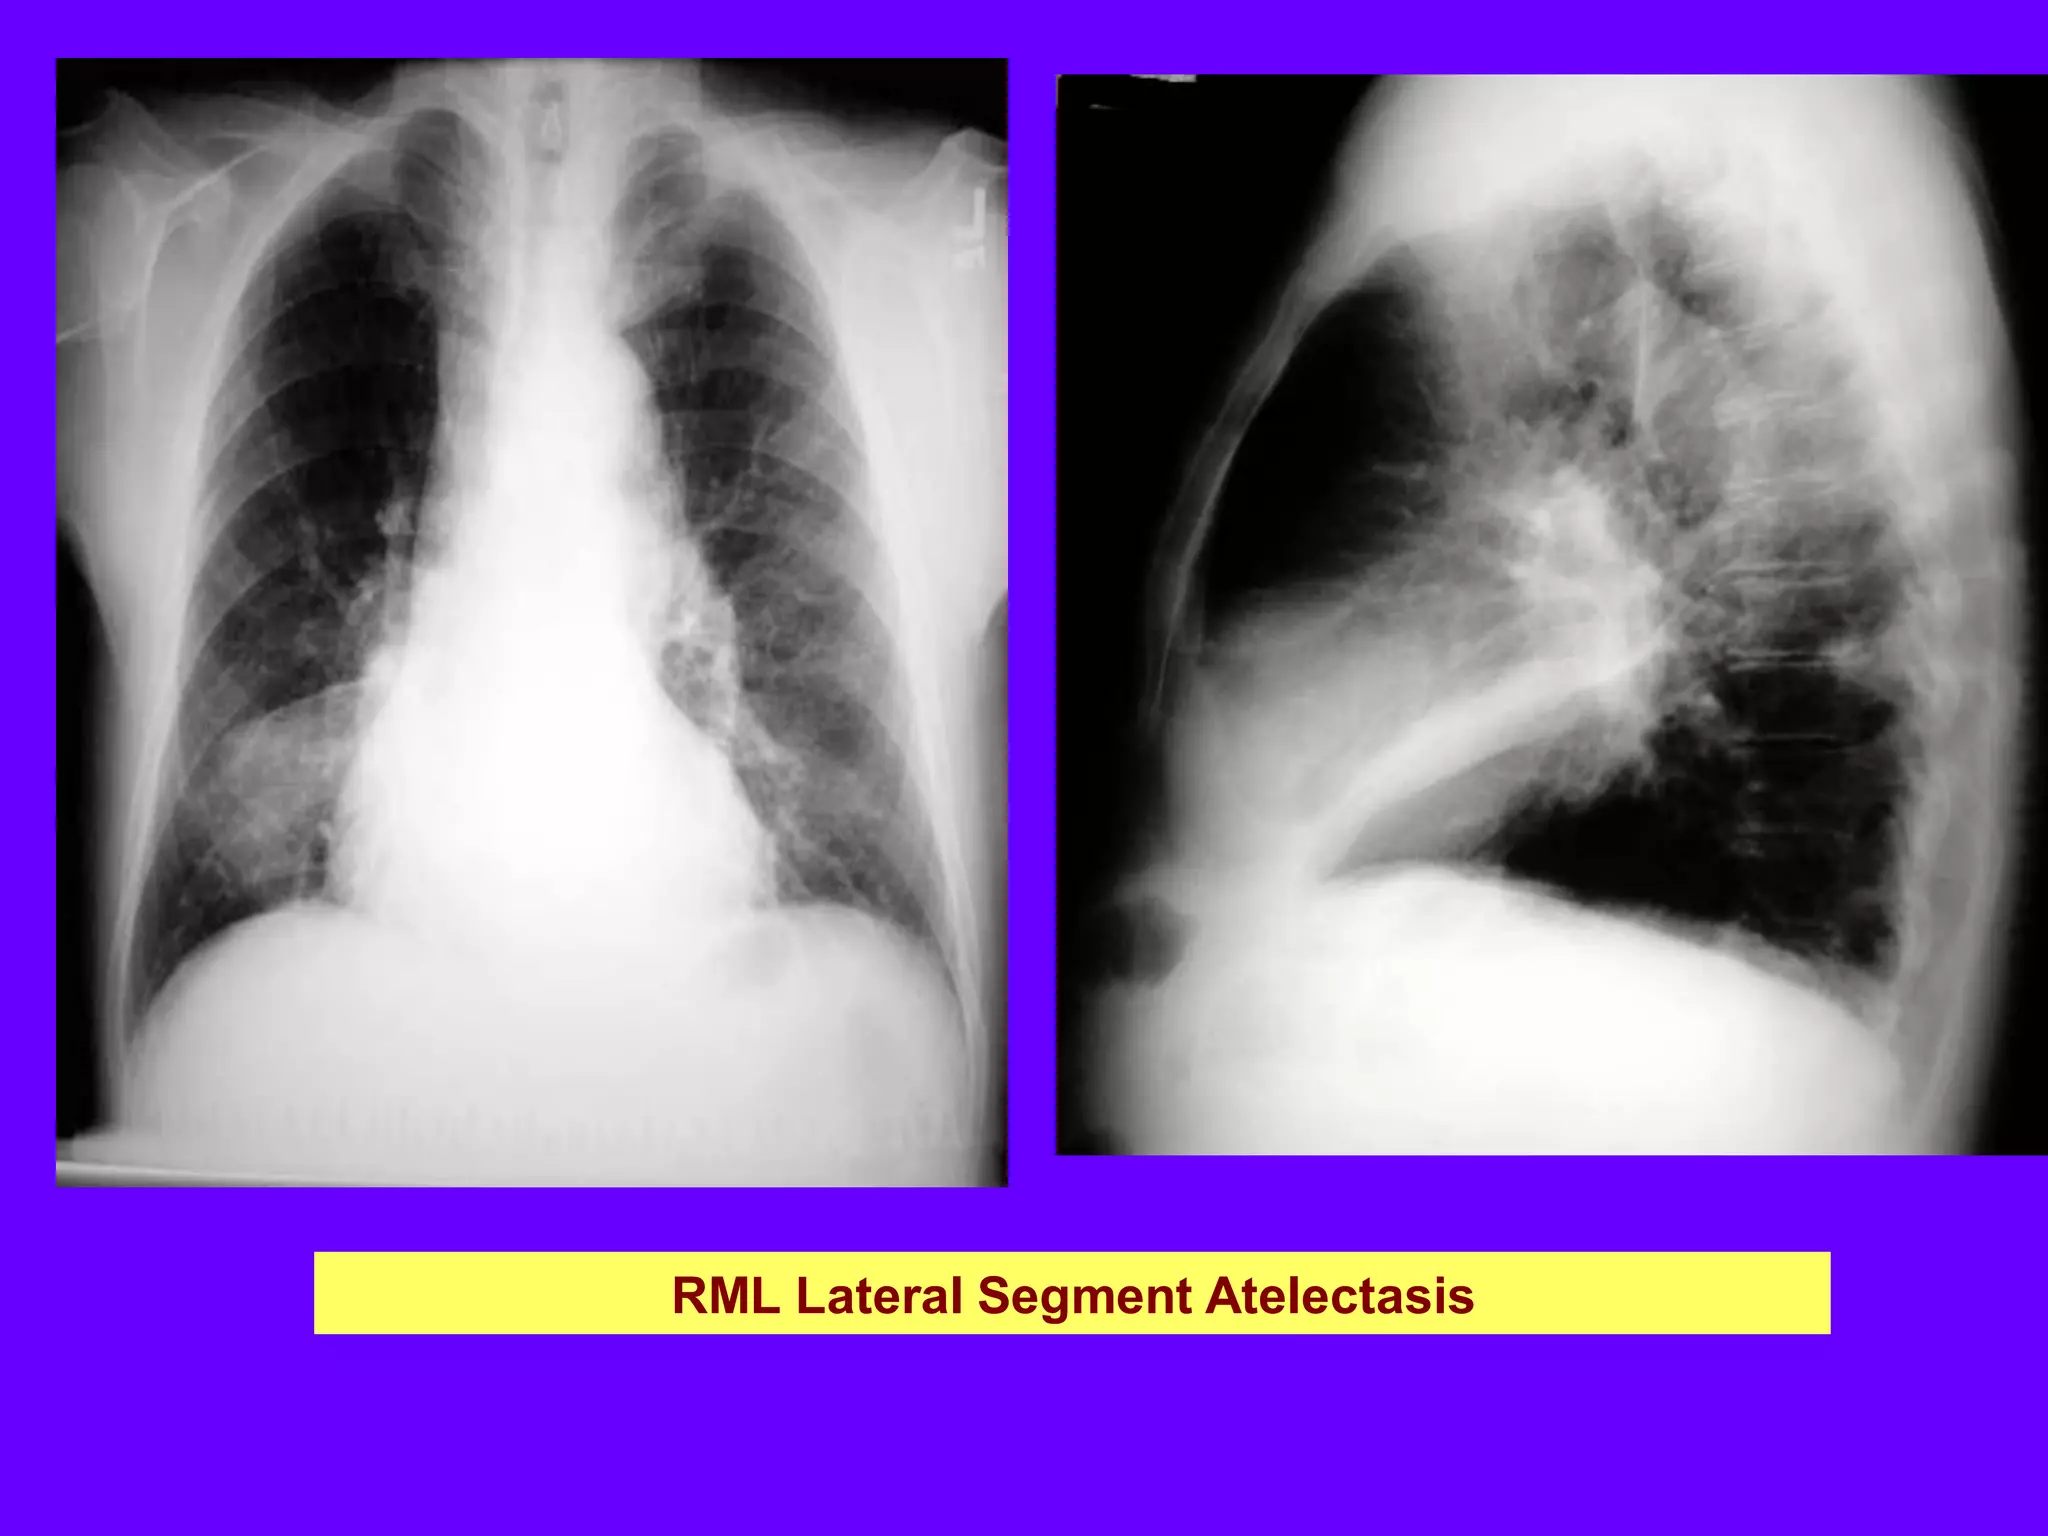

RML Atelectasis

Vague density in right lower lung field, almost normal

RML atelectasis in lateral view, not evident in PA view

Vague density in right lower lung field (almost a normal film).

Dramatic RML atelectasis in lateral view, not evident in PA view. Movement of

transverse fissure.

RML Lateral Segment Atelectasis